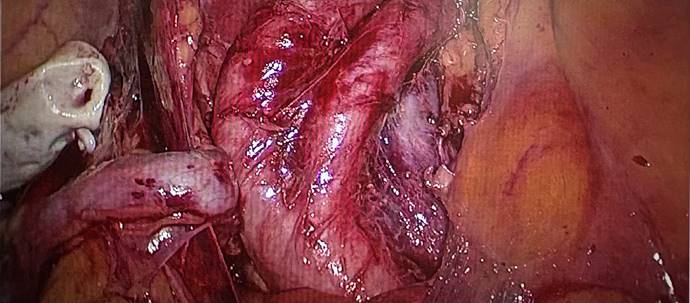

手术采用完全腹腔镜路径进行,团队克服了腹腔镜下空间操作受限、缝合重建难度大等挑战,精准完成了根治性膀胱切除、标准淋巴结清扫以及高难度的“全去带乙状结肠原位新膀胱”构建。整个手术过程流畅,出血量显著少于传统开放手术(约200ml)。术后,患者恢复顺利,生命体征平稳,已开始进行新膀胱功能训练。